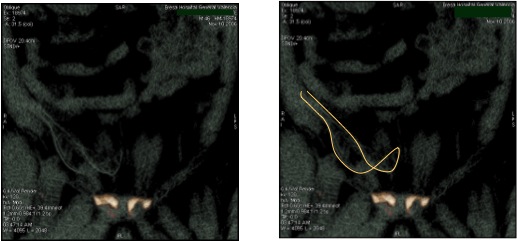

En estas imágenes se aprecia la malla doblada sin expandirse completamente en el espacio preperitoneal.

La evaluación del anillo de memoria de poliéster de la malla mediante el tac 3D nos permite comprobar la expansión y el posicionamiento de las mallas sin añadir agrafes u otros artefactos.